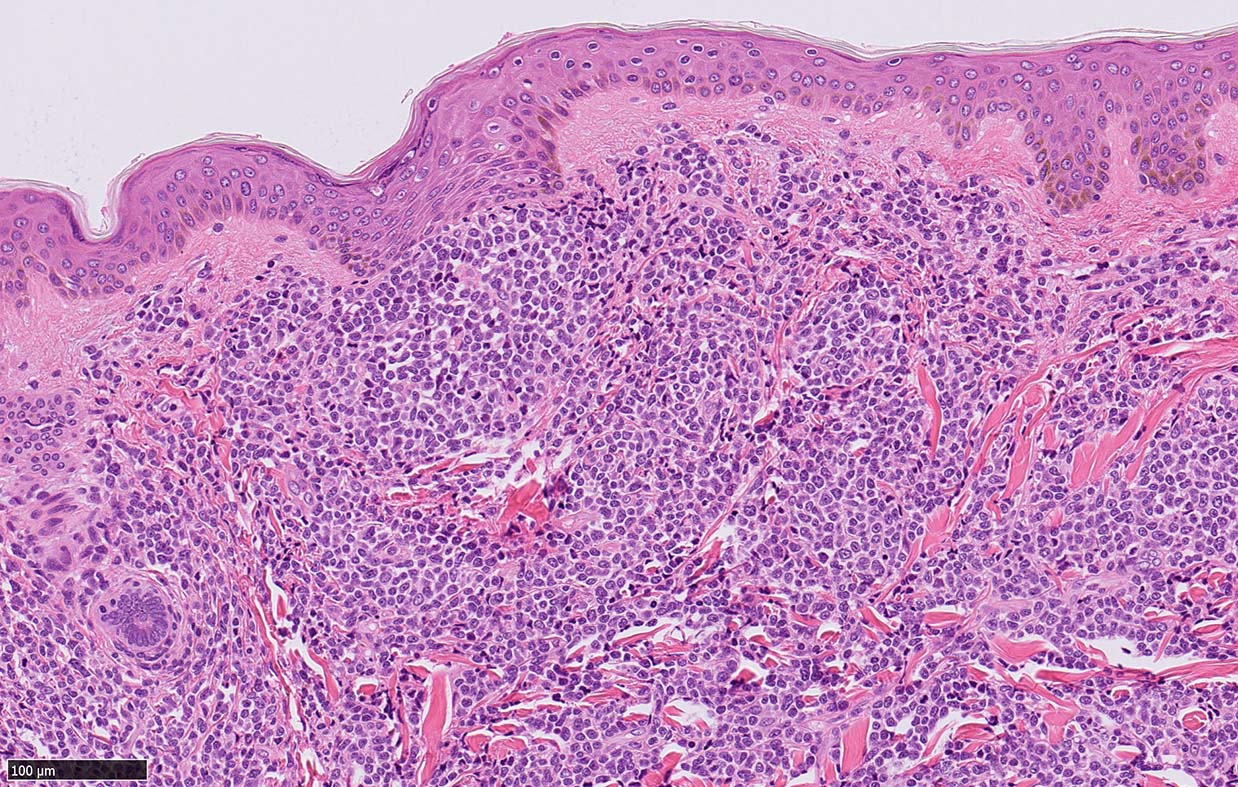

皮膚病変

blasticという名前から「大型細胞」を想起するが, この症例のようなclassical typeの細胞は思ったほど大きくはない. CD123陰性リンパ球とくらべてもあまり大きくないことがわかる.(散在する大型細胞はlysozyme+)

形態は均一で多型はめだたない.

皮膚病変は64-100%の症例で認められ皮膚病変が契機となり診断されることも多い.

マクロ所見は多彩で, 孤在性から播種性の分布を呈し, 腫瘤, 局面, 紅斑いずれの形態もとりえる.

腫瘍細胞は真皮を主座として, 皮下脂肪織まで, びまん性かつ単調monotonousに増殖することが多く, 表皮向性はみられない. 本例では血管や付属器中心あるいは脂肪織内に結節状の浸潤増殖を示した.

本例皮膚真皮増殖細胞はCD4+, CD56+, CD123+, CD303+, lysozyme(-). がん研有明病院, Sakamoto K, Takeuchi K先生にconsultationを行い, TCF4, TCL1の陽性が確認された.(consultationを受けていただいた両先生に深謝いたします.)